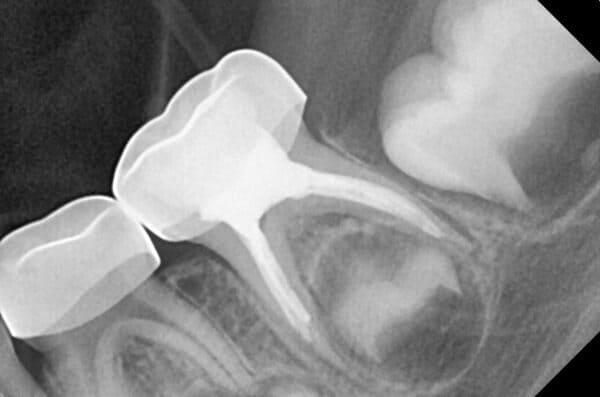

Дівчинка 7 років, перше вересня, гойдалка… Вивих постійного зуба: якщо в такій ситуації зволікати, дитина може втрати постійний зуб назавжди. Батькам порекомендували нас і пацієнти одразу приїхали. Через складність і травматичність процедур вирішено проводити лікування в анестезіологічному супроводі. Зуб поставлений на місце (репонований), проведена хірургічна обробка і ушивання рани губи. Останнє фото через рік після травми: зуб на місці і корінь продовжує розвиватись, губа повністю загоїлась